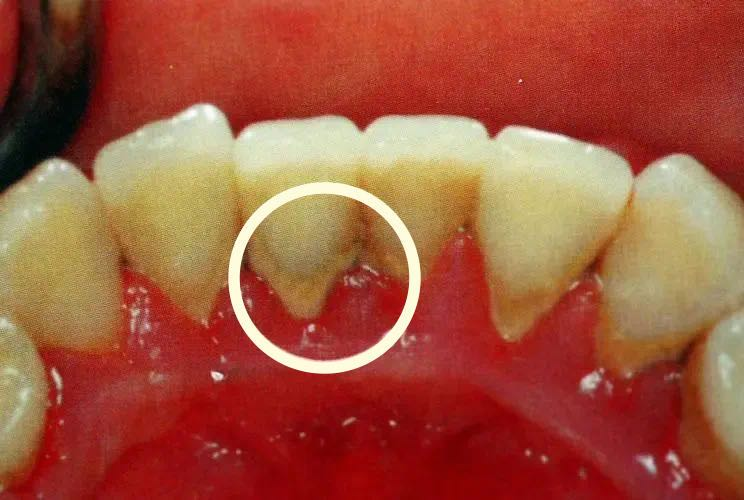

如果没有定期去口腔诊所洗牙,那么牙结石就会越来越多,压迫牙龈。牙龈开始红肿,这个阶段,刷牙很容易见血。

如果对牙龈肿痛出血不太在意或者简单地当作“上火”来处理,那么牙龈就会开始萎缩,牙槽骨被吸收破坏,这时牙齿已经轻微松动了。